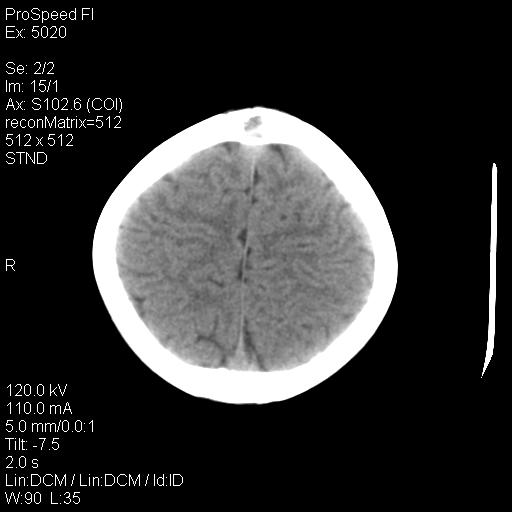

标题: PED1637:M 6Y 顶部无痛性包块两月。 [打印本页]

标题: PED1637:M 6Y 顶部无痛性包块两月。

2、颅骨局部缺失,边缘光滑、整齐

颅骨的病损表现为内外颅骨板层不规则的锋利的破坏,形成“斜边缘”,有一定的特点

颅骨为好发部位,生长缓慢,常位于顶骨、枕骨及颞骨,表现为颅骨缺损,呈圆形或椭圆形,边界清,无硬化

事发冠状缝与矢状缝交界区,密度较低,考虑表皮样囊肿可能性大,其次不除外嗜酸性肉芽肿